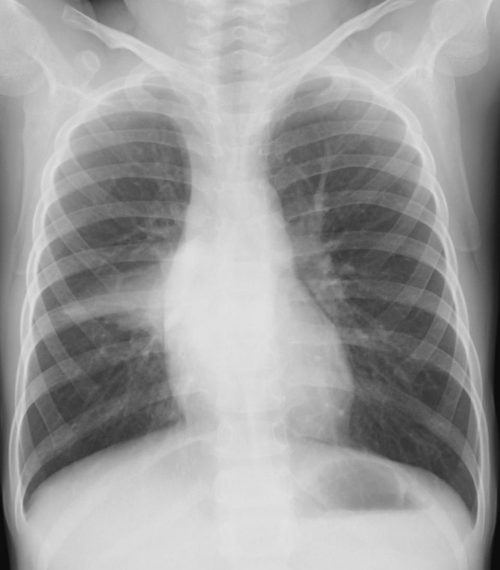

外来でよくみられる肺炎、マイコ・クラミジア・肺炎球菌・ウイルス(RSウイルス・hMPV・インフルエンザウイルスA・B)について実際に経験、外来で治癒した症例を提示します。軽症な変化のものが大多数ですが中には重症なものも紛れていて、注意が必要になります。

【マイコプラズマ肺炎】